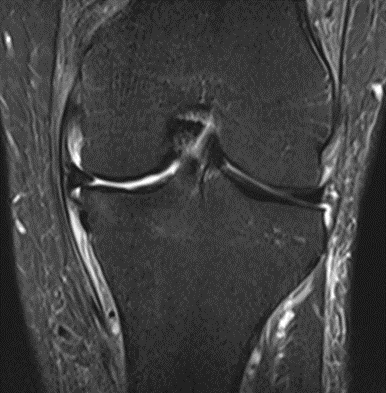

MRI scans illustrating the improvements regarding Group 2 are presented below, showing pre-treatment images with evident cartilage defects, pronounced bone marrow edema, and synovial inflammation, followed by post-treatment scans demonstrating improved joint structure, reduced edema, and decreased inflammation (Figures 12-29).

Figure 16: Female, 76 years, pre-intervention MRI.

Figure 17: Female of figure 16, two-month follow-up MRI: MSC plus ChondroFiller® liquid.